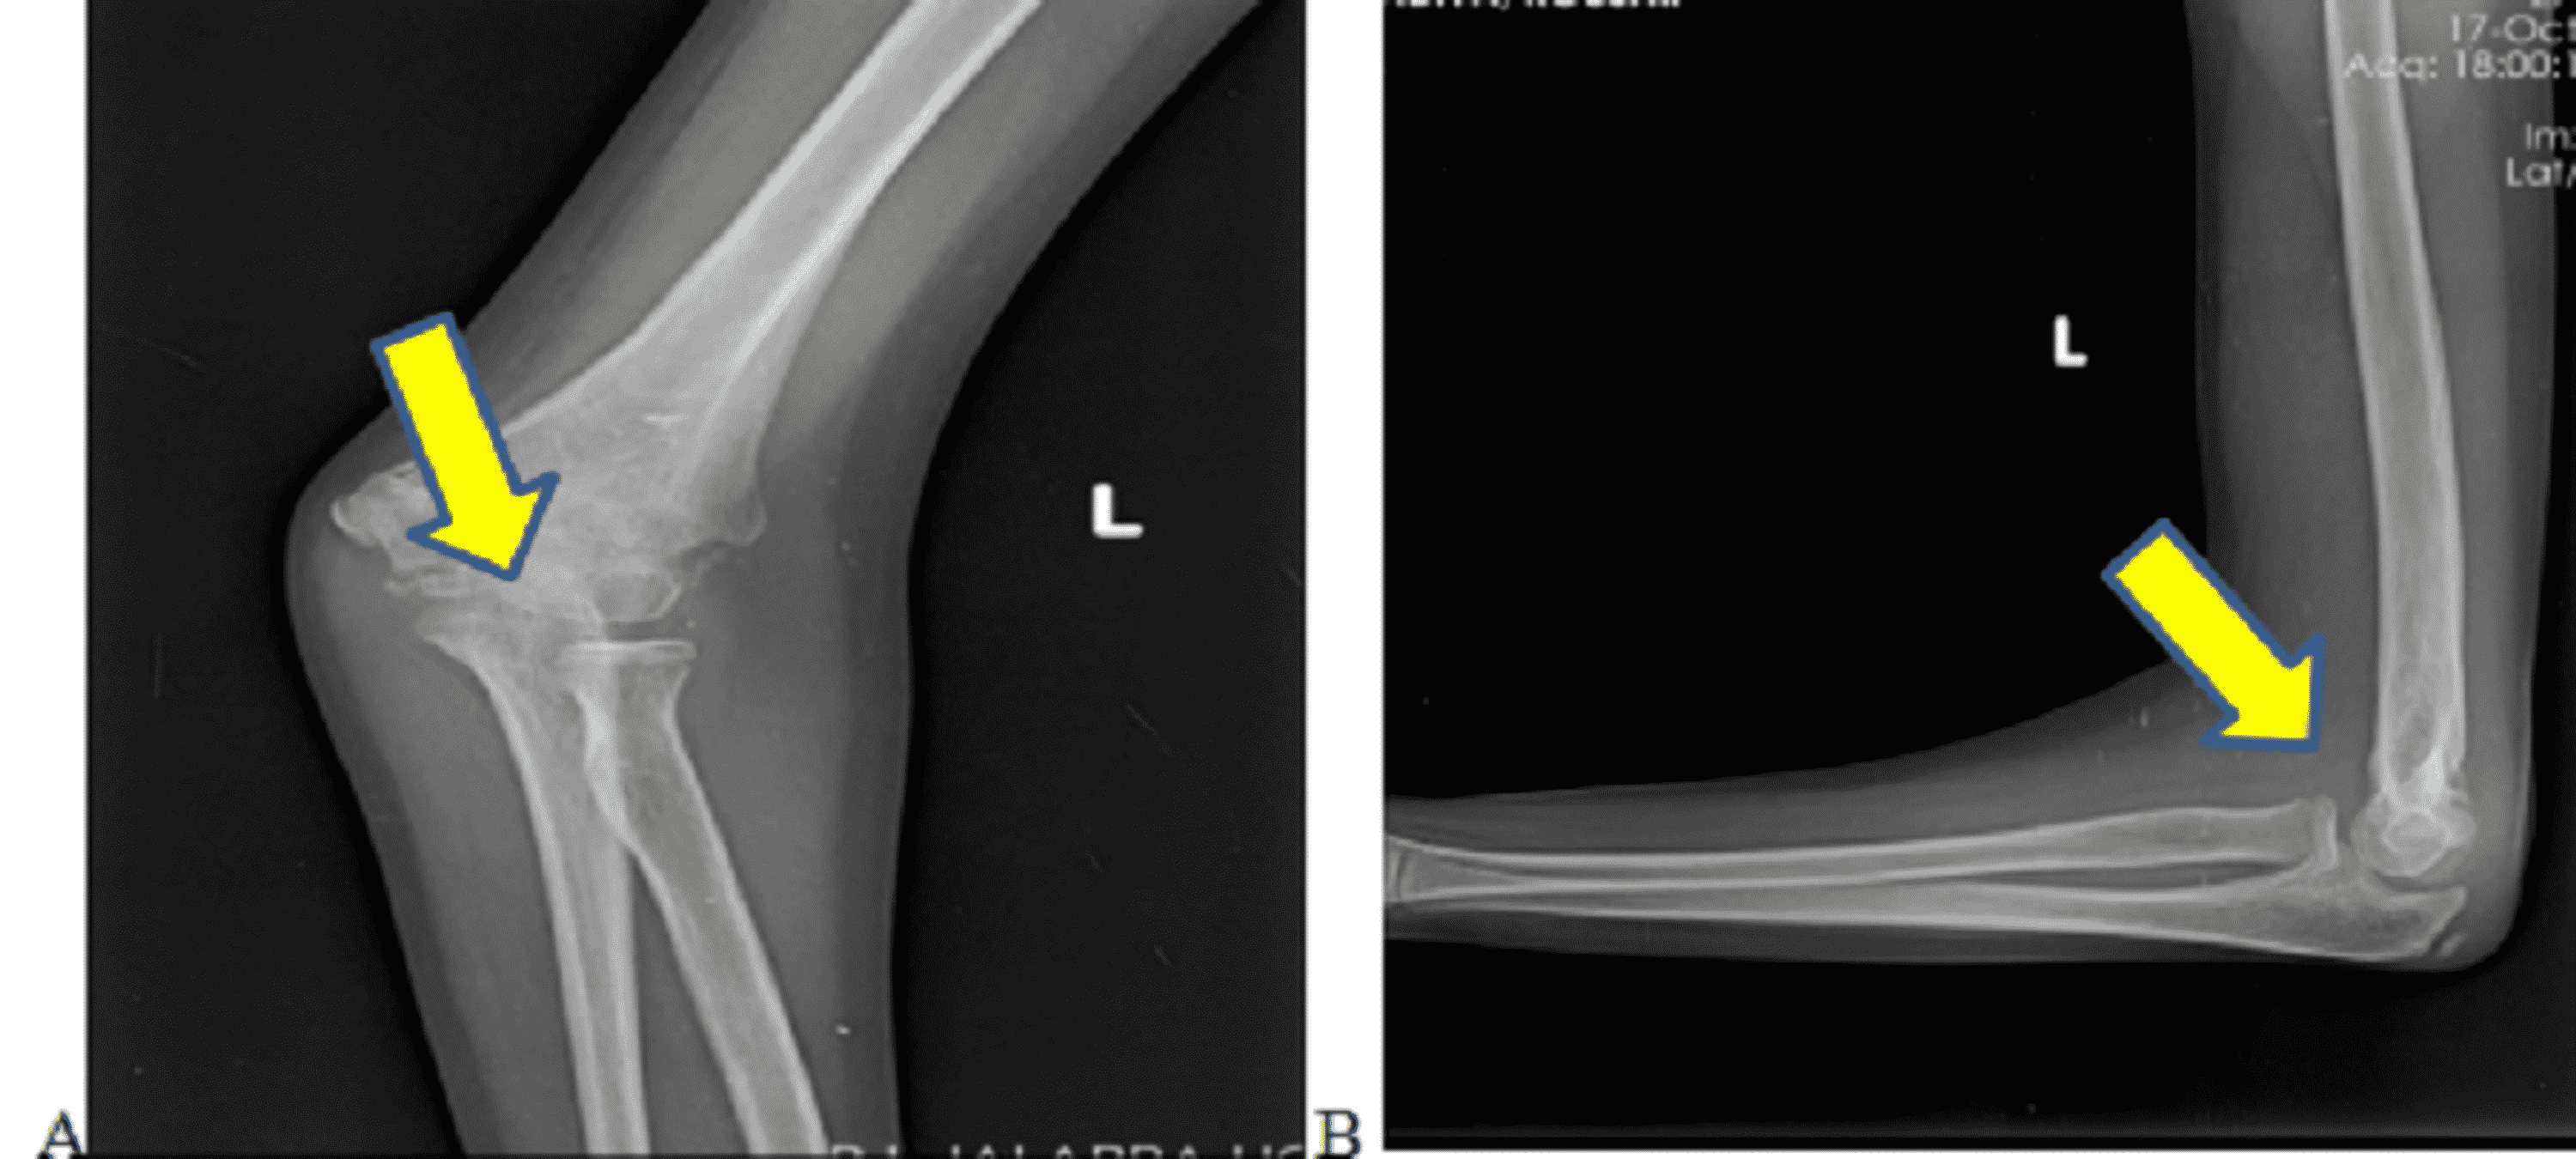

A sevenyearold boy with a PFPSpositive displaced extension type

A sevenyearold boy with a PFPSpositive displaced extension type Extension Type Supracondylar Fracture Supracondylar fractures are initially divided into two types, depending on the direction of displacement of the distal fragment: The majority of all extension type supracondylar fractures show a rupture of the anterior (cubital) and medial periosteum (as shown in these x. Distal humerus fractures are traumatic injuries to the elbow that comprise of supracondylar fractures, single column fractures, column fractures. Extension Type Supracondylar Fracture.